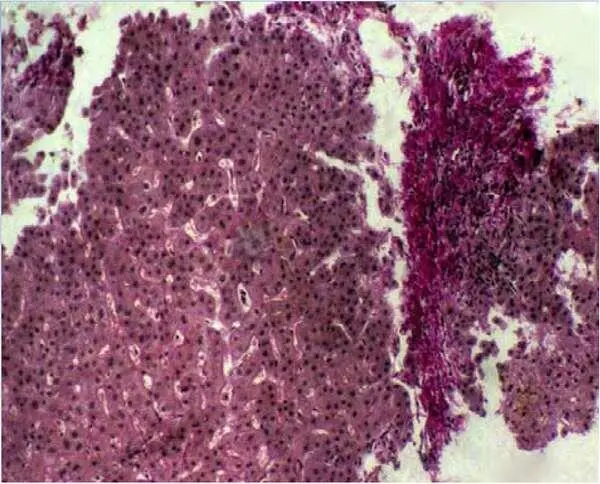

Рисунок 9 – Фрагментация биоптата печени. Окр.: гематоксилином и эозином. Х200